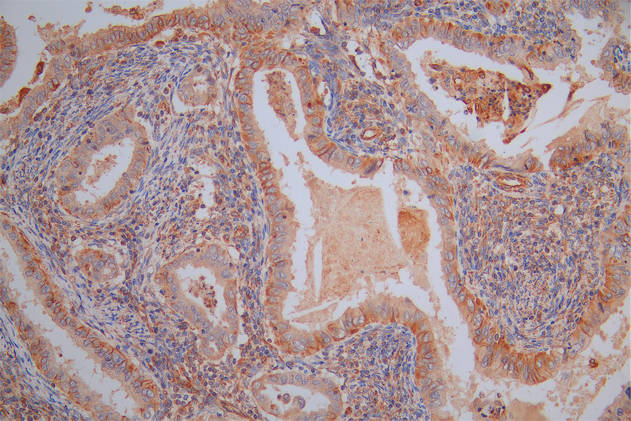

圖片:

應用范圍:ELISA, IHC, IF

Application Recommended Dilution IHC 1:20-1:200 IF 1:50-1:200 -